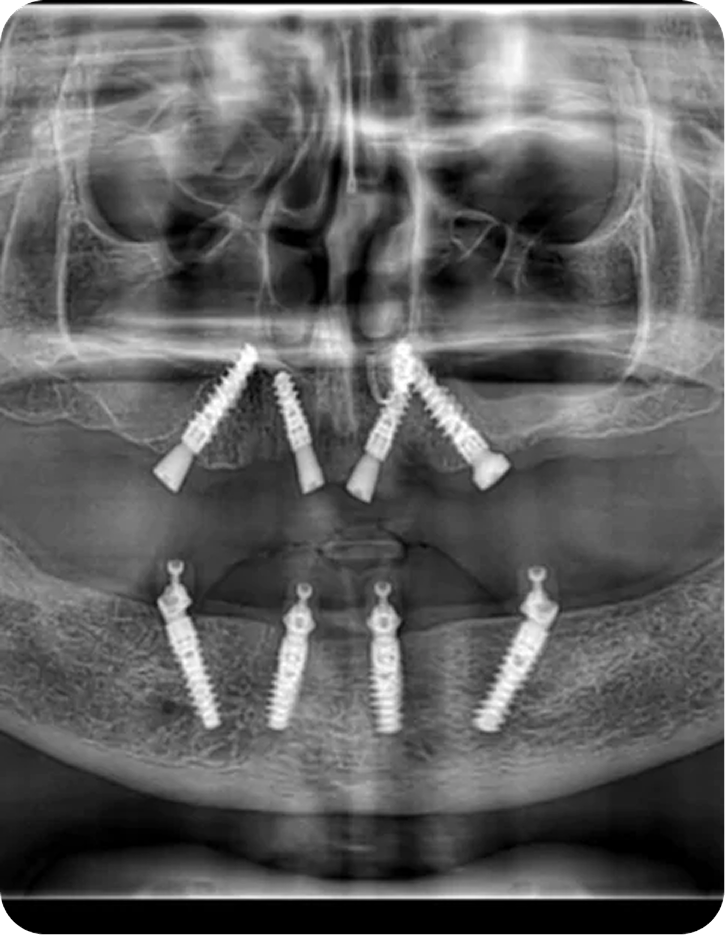

Since year 2000 we are Centre of excellence in implantology .We have done thousands of full mouth dental implant cases in last 25 years .We have a team approach where experienced implant surgeons , prosthodontists , maxillofacial surgeons , digital restorative dentists and lab technicians work together to deliver world class fixed teeth. We use multiple implant option from case to case. Some need All-on-4, some need All-on-6 or All-on-8 in selective cases.

It is a revolutionary concept in which only four implants support an entire arch of teeth. It is minimally invasive and cost-effective.

It is an advanced technique in which six implants support a full arch of teeth. It ensures superior stability, durability, and improved chewing function.

The procedure of Full Mouth Dental Implants involves, extraction of teeth or root of the existing teeth if any, CBCT Scans and X-ray, Planning of implant placement, procedure of Implant placement, healing, temporary prosthesis and then a final prosthesis restoration, giving a perfect smile, functionality and appearance.

How are dental implants replaced in the mouth?

Implants are placed based various factors, prominent being 0the bones density for implant placement, every procedure is done using the advanced technology, such as CBCT guided implant placement, while also Implant torque is considered crucial. These all things are considered to place implants strategically to support Full Mouth Teeth Replacement, for functionality, durability and aesthetics.